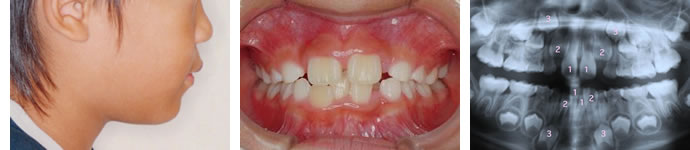

■初診来院時 (観察開始時 ・装置は入れません) 6歳11ヶ月

下の歯の1本が他の歯の後ろに隠れるほどの叢生症状と、上の前歯に隙間があることを気にして相談に見えられました。

レントゲンを撮ってみると、ほとんどの乳歯の下に「永久歯の種」と言われるものができており、これから変化していく歯並びの状態がある程度予測されますが、今の段階ではいかなる方法を用いても永久歯列完成時(12歳頃)における本格的矯正治療は避けることができないと判断しました。

よって矯正装置は何も入れずに永久歯に生えかわってしまうまで年一回程度の定期観察のみ行うこととしました。